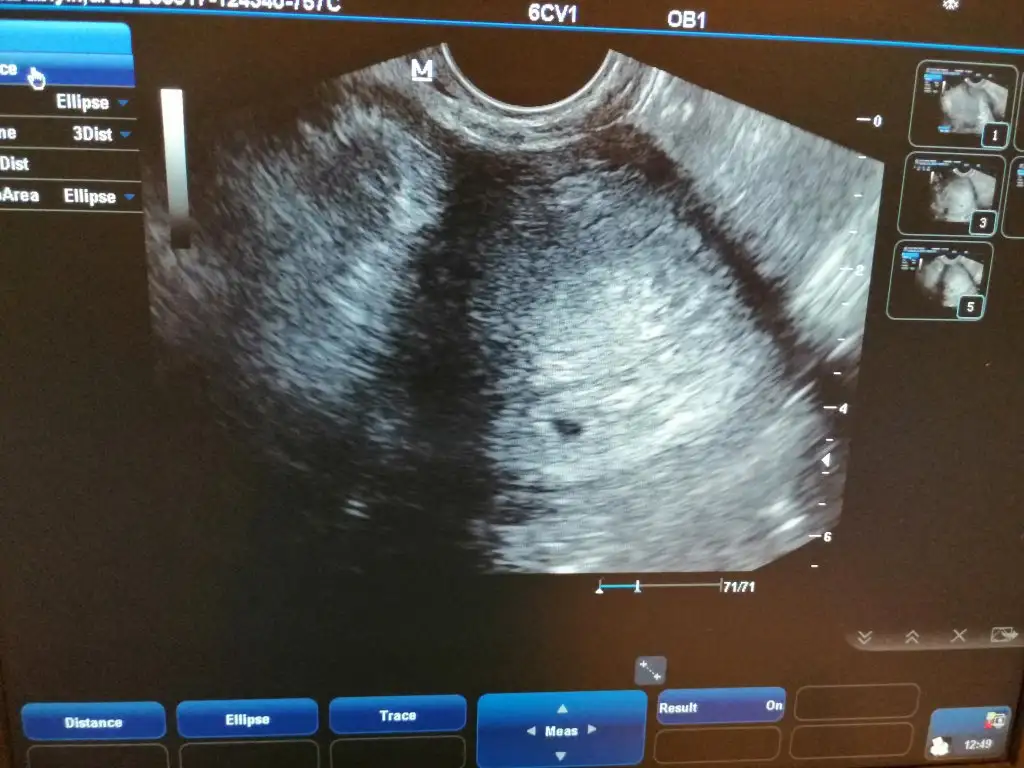

6. Haftadan itibaren karından bakılarak duyuluyormuş canım hadi hayırlısı hepimiz içinBen de tam 7+0 için randevumu aldım erken sanıyordum . Ne güzel 6. Haftada duymussunuz çok şükür![]()

AA neden sonlandırmak mı gerekiyor ki?Kızlar selam. Bugun gittim ultrasona. 2 kese göründü. Karindan duyamadi kalp atışı alttan bakti ikisindede kalp atışı var. Benimilk hamileligim sıkıntıliydi. Gebelik zehirlenmesi yasadim kizimda gelişim.geriligi. Tüp bebek doktorum 2 embriyo koyalim ikisi de tutarsa birini sonlandiririz demişti. Daha dönüş yapmadi bana. Çok zor bir durumun icindeyim ya sevinemedim.bile.